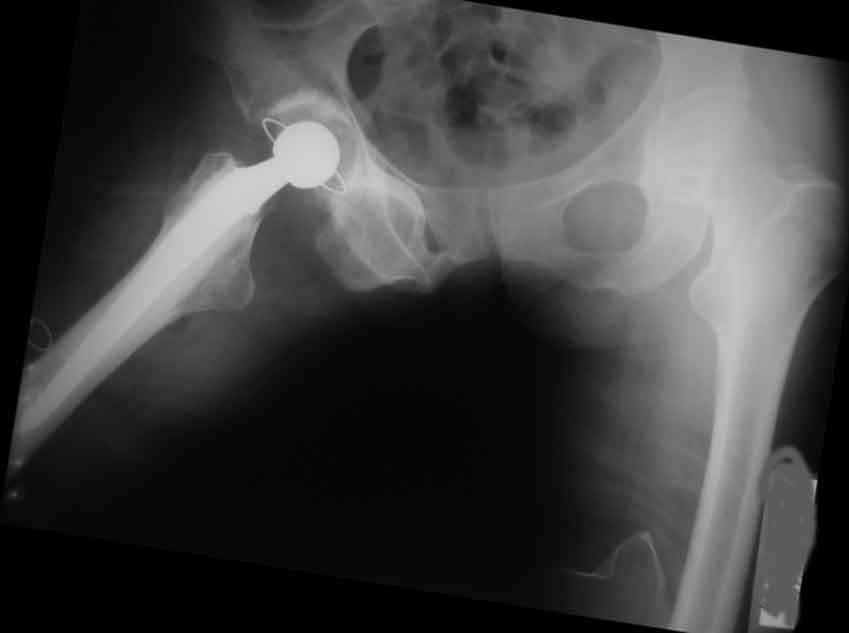

[Ortho] застарелый запирательный вывих бедра

пока сложно сделать нормальный снимок после операции, это первый